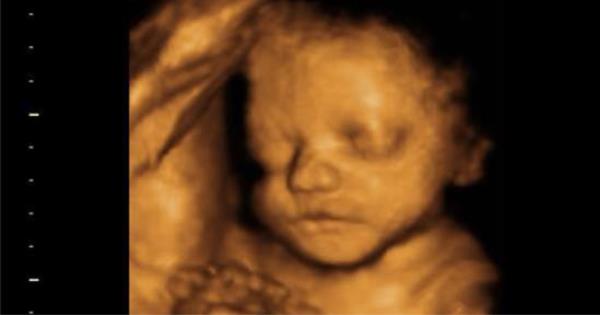

導讀:孕婦在產檢時,都會做很多的血液、尿液和超音波檢查,用來確保胎兒的健康和成長。有一種檢查是非必要的,但它能讓妳清楚看到寶寶的臉以及手腳,也就是3D超音波。清晰的3D圖像可以讓妳看到孩子的長相。 一、何時應該做3D超音波檢查 1、最佳檢查時機 做3D超音波檢查最好的時間是在懷孕26~30週之間。26週之前,胎兒的皮膚下會有很多的脂肪,因此做3D只會照到他臉部的骨骼圖像。 2、在三十週之後 當寶寶超過30週之後,他的頭有可能會深入到骨盆中,因此這時候做3D超音波可能無法清楚的照到寶寶臉部的圖像。  3D超音波可以看到寶寶的臉。 3、若有胎盤前壁 假如妳有胎盤前壁的情況,胎盤在妳子宮的前壁上,因此妳需要等到28週之後再做3D超音波,才能照到清楚的圖像。